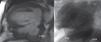

Case reportA 72-year-old male was referred to our institution due to a two-year history of progressive dyspnea. He had undergone inferior LVA resection and left internal mammary artery to left anterior descending artery (LAD) bypass eighteen years earlier. Physical examination revealed a grade II holosystolic apical murmur and the ECG showed previously unnoticed atrial fibrillation. Laboratory findings and chest radiography were unremarkable. Transthoracic echography revealed a dilated left atrium with mild mitral regurgitation. Left ventriculography showed a large bilobulated inferior aneurysm with dyskinetic wall motion (Figure 1A). Left ventricular systolic function was severely depressed, with an ejection fraction (EF) of 0.35 in the non-aneurysmal segments. Coronary angiography showed severe stenosis in the proximal LAD and occlusion of the right coronary artery. The internal mammary graft was patent. Magnetic resonance imaging (MRI) revealed a dilated left ventricle (LV) (163 ml/m2) with severely depressed global contractility (EF 0.20) and a large inferior aneurysm. An additional smaller basal pouch was also identified (Figure 1B).